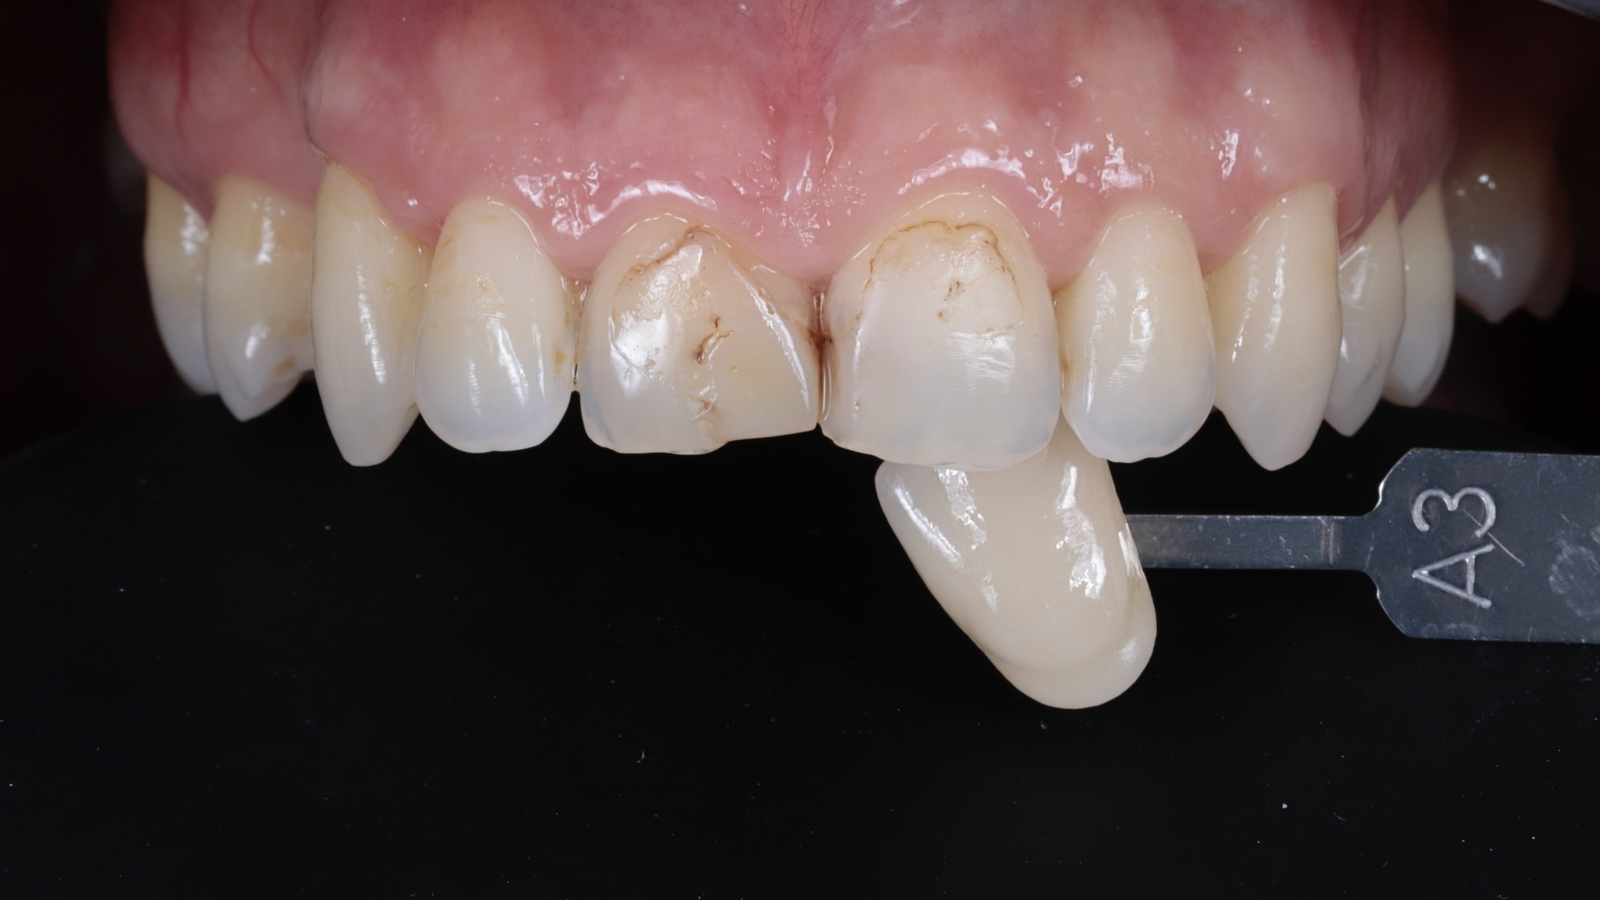

The patient presented with insufficient composite fillings on tooth 11 and 21. The goal was to restore the central incisors with a single shade to achieve a natural, aesthetic appearance.

Shade selection is made easy with Venus Pure Shades: just choose between LIGHT, MEDIUM, DARK and BLEACH. The shade adaptation of Venus Pearl leads to a seamless integration in the natural tooth shade. Using the conversion scale, the MEDIUM shade (matching VITA®*) was selected to match this patient's natural teeth.